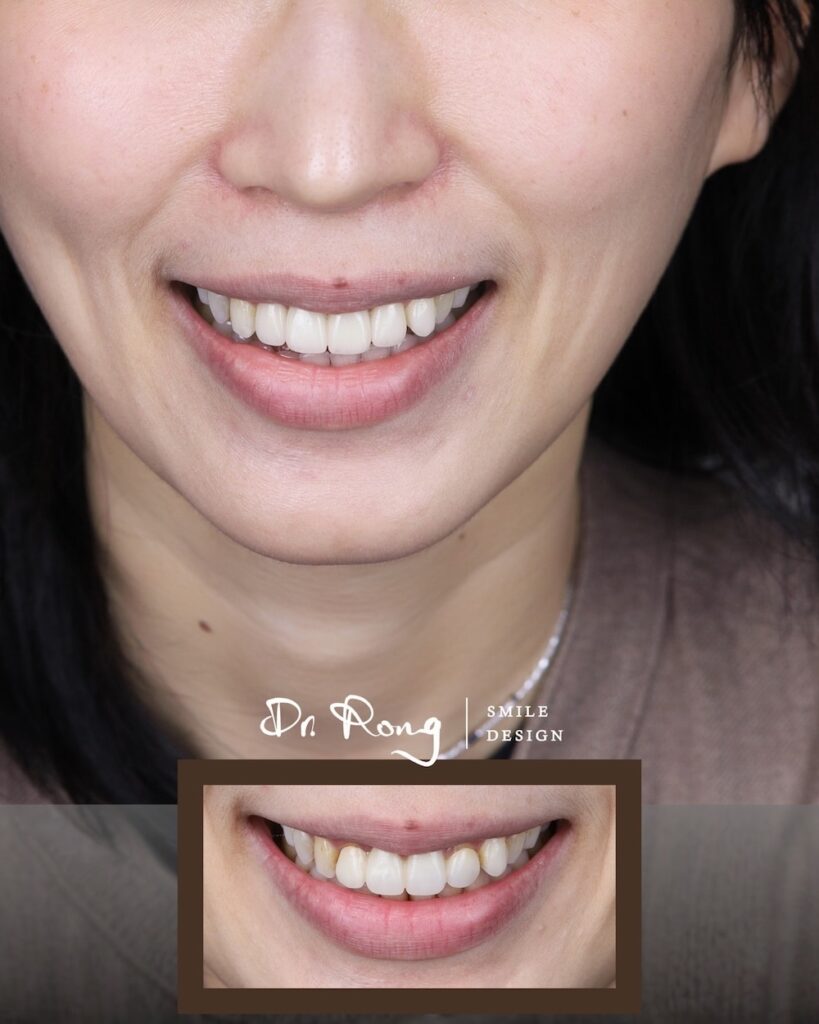

許多患者來到診間,並非因為「牙齒不夠白」,而是因為舊假牙「太像假的」。門牙假牙顏色不自然、偏白甚至呈現死白,或是假牙邊緣不密合、出現黑邊,都會讓笑容看起來不協調。

真正的數位美學設計,在門牙假牙重做過程中,不只是更換材料,而是透過精準的軸向校正與牙齦健康管理,讓門牙重新融入面部比例,達成局部換新卻完全不突兀的自然感。

在這個案例中,患者帶著對舊假牙的不滿意來到悅庭找我。透過數位口腔掃描與臨床觀察,我們發現過往治療留下了三個美觀與健康上的遺憾:

- 假牙顏色不自然、偏灰:傳統材質缺乏真牙的透光感,在自然光下容易顯得生硬突兀。

- 牙齦發炎與邊緣發黑:舊假牙邊緣不密合,長期刺激導致牙齦紅腫發炎,甚至出現萎縮與邊緣黑影。

- 門牙角度與弧度不理想:假牙軸向過度外翻,且整體弧度偏斜,讓笑容失去了該有的溫潤感。

在門牙全瓷冠重建過程中,我們微調了每一顆牙齒的生長角度。將原本過度外傾的門牙向內收斂,並校正傾斜的齒緣弧度。這僅僅 4 顆牙齒的改變,就讓患者整體的氣質從「生硬」變得「柔和」。

我們選用能遮住內層齒色卻也足夠透光的陶瓷材質,模擬自然齒質的漸層色澤。透過精密的色彩校正,確保這 4 顆新成員能完美隱身在其他天然牙齒中,達成真正「融入式」的美感。

看著患者在鏡子前露出不再遮掩的燦爛笑容,這就是美學牙醫最有成就感的時刻。這不只是 4 顆門牙的更新,更是一次自信心的重塑。